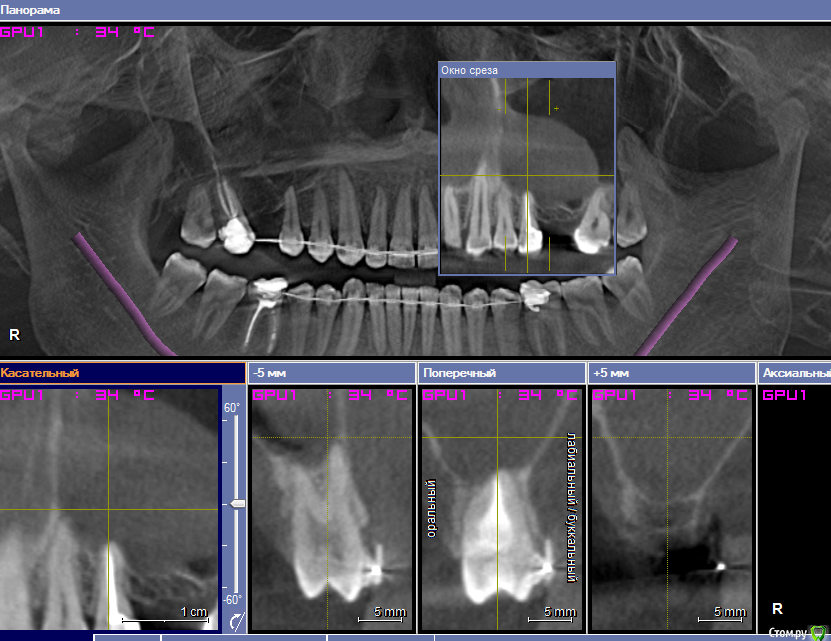

___49___ Опубликовано 15 февраля, 2019 Поделиться Опубликовано 15 февраля, 2019 Уважаемые коллеги , прошу совета, или просто мыслей в слух - как поступить в данной клинической ситуации ? фото прикладываю ниже , хотелось бы выполнить открытый синус слева с одновременным удалением кисты - как это правильнее воплотить технически , обязательна ли гистология , какие "подводные" камни могут быть , какие материалы лучше иметь под рукой ? Справа пока не определился - может ретроградку сделаю через окно с открытым синусом одновременно может удалю ..не суть - пока вопрос по левой стороне . спасибо . Ссылка на комментарий

pit Опубликовано 16 февраля, 2019 Поделиться Опубликовано 16 февраля, 2019 Уважаемые коллеги , прошу совета, или просто мыслей в слух - как поступить в данной клинической ситуации ? фото прикладываю ниже , хотелось бы выполнить открытый синус слева с одновременным удалением кисты - как это правильнее воплотить технически , обязательна ли гистология , какие "подводные" камни могут быть , какие материалы лучше иметь под рукой ? Справа пока не определился - может ретроградку сделаю через окно с открытым синусом одновременно может удалю ..не суть - пока вопрос по левой стороне . спасибо .Можно отпунктировать и поднять, это самый простой вариант. Или удалить через разрез слизистой, ретенционная киста легко отделяется от слизистой. Но с юридической точки зрения правильнее направить к ЛОР на эндоскопию и через 2 мес выполнить ОСЛ. 6 Ссылка на комментарий

Nazim_NV86 Опубликовано 16 февраля, 2019 Поделиться Опубликовано 16 февраля, 2019 (изменено) Если такого лора нет поблизости, то удалить через разрез слизистой, ретенционная киста легко отделяется от слизистой.Мне приходится именно так и делать. Судя по всему соустье там рабочее. Поэтому дополнительное окно над 25 позволит убрать оболочку. Алгоритм такой:1. Делаем окно над 25 и иглой откачиваем содержимое. 2. Делаем окно над 26 и отслаиваем3. Надрез слизистой над 25 и извлечение оболочки4. Мембрана, графт, имплант и т.д.Если есть ещё варианты, всегда готов к новым методам. с юридической точки зрения правильнее направить к ЛОР на эндоскопию и через 2 мес выполнить ОСЛ. Всегда об этом думаю. Даже в процессе операции Изменено 16 февраля, 2019 пользователем Nazim_NV86 2 Ссылка на комментарий

___49___ Опубликовано 26 февраля, 2019 Автор Поделиться Опубликовано 26 февраля, 2019 #Проверил премоляр и моляр на витальность #Пролечил или перелечил по необходимости каналы #Направил бы к ЛОРу на эндоскоп А дальше по плану. Но с юридической точки зрения правильнее направить к ЛОР на эндоскопию и через 2 мес выполнить ОСЛ - вот по этому варианту и пойдем , только сначала РВК в области 17 зуба ( уберем всю одонтогенность ) и через 2 недели к ЛОРу на эндоскопию , затем ОСЛ . Спасибо Уважаемые коллеги . Nazim_NV86 все читаю - беру на заметку 1 Ссылка на комментарий